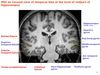

6 layers of cerebral cortex

Molecular

External granular

External pyramidal

Internal granular

Internal pyramidal

Multiform